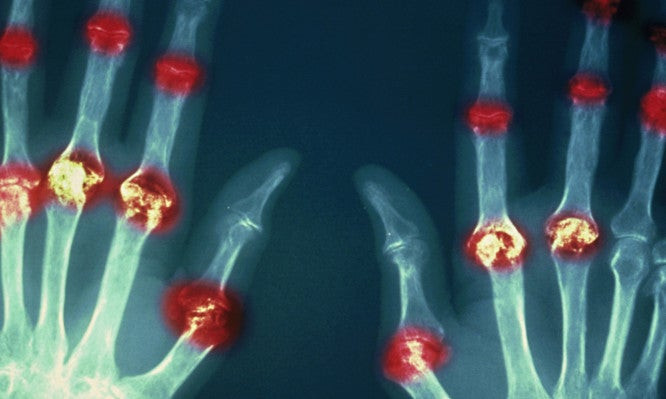

Ρευματοειδής αρθρίτιδα: Συμπτώματα, διαθέσιμες θεραπείες και μέτρα πρόληψης

Στο πλαίσιο των αυτοάνοσων νοσημάτων, δηλαδή των ασθενειών κατά τις οποίες το ανοσοποιητικό σύστημα του οργανισμού επιτίθεται λανθασμένα σε υγιή κύτταρα ιστών, εκλαμβάνοντας αυτά σαν ξέν...